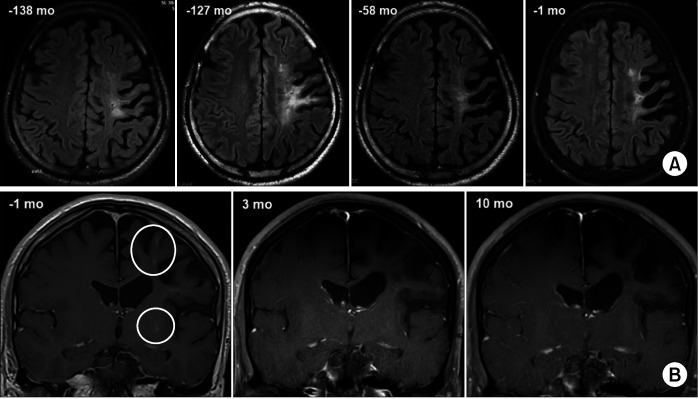

Neuro-Behçet's disease (NBD) represents a significant complication of Behçet's syndrome, potentially leading to elevated mortality and disability rates. The standard treatment for parenchymal NBD typically entails administering high-dose corticosteroids to prompt rapid-onset effects, coupled with immunosuppressants to prevent subsequent relapses. A 48-year-old male with NBD presented with progressively worsening dysarthria over 9 months. This patient experienced increased intraocular pressure while using glucocorticoids, which worsened his pre-existing glaucoma. The patient had a prior diagnosis of NBD and presented with progressive dysarthria over a period of nine months, leading to a brain magnetic resonance imaging (MRI) scan. The brain MRI revealed multifocal punctate high signal intensities in the left frontoparietal area, insula, and basal ganglia. Instead of the standard steroid pulse therapy, the patient received adalimumab-cyclophosphamide combination as an alternative induction therapy. Subsequent serial brain MRI scans exhibited no emergence of new lesions, and the patient remained devoid of clinical relapses even after 17 months from the commencement of induction treatment. Adalimumab-cyclophosphamide combination could be used as a corticosteroid-free induction strategy for NBD. Further investigations are warranted to establish the most suitable combination regimen.